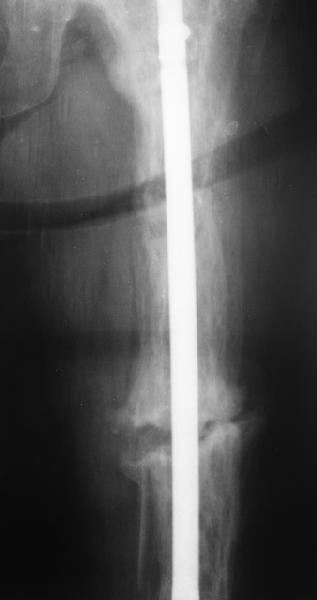

Еще один пример. Пациентка с юга России, прислала рентгенограммы через

год. На сегодня прошло 2 г. 8 мес. после операции. Несмотря на не очень

убедительный процесс сращения, пациентка ходит. Учитывая остеопороз при

Педжете, решили, что динамизировать вообще не нужно.